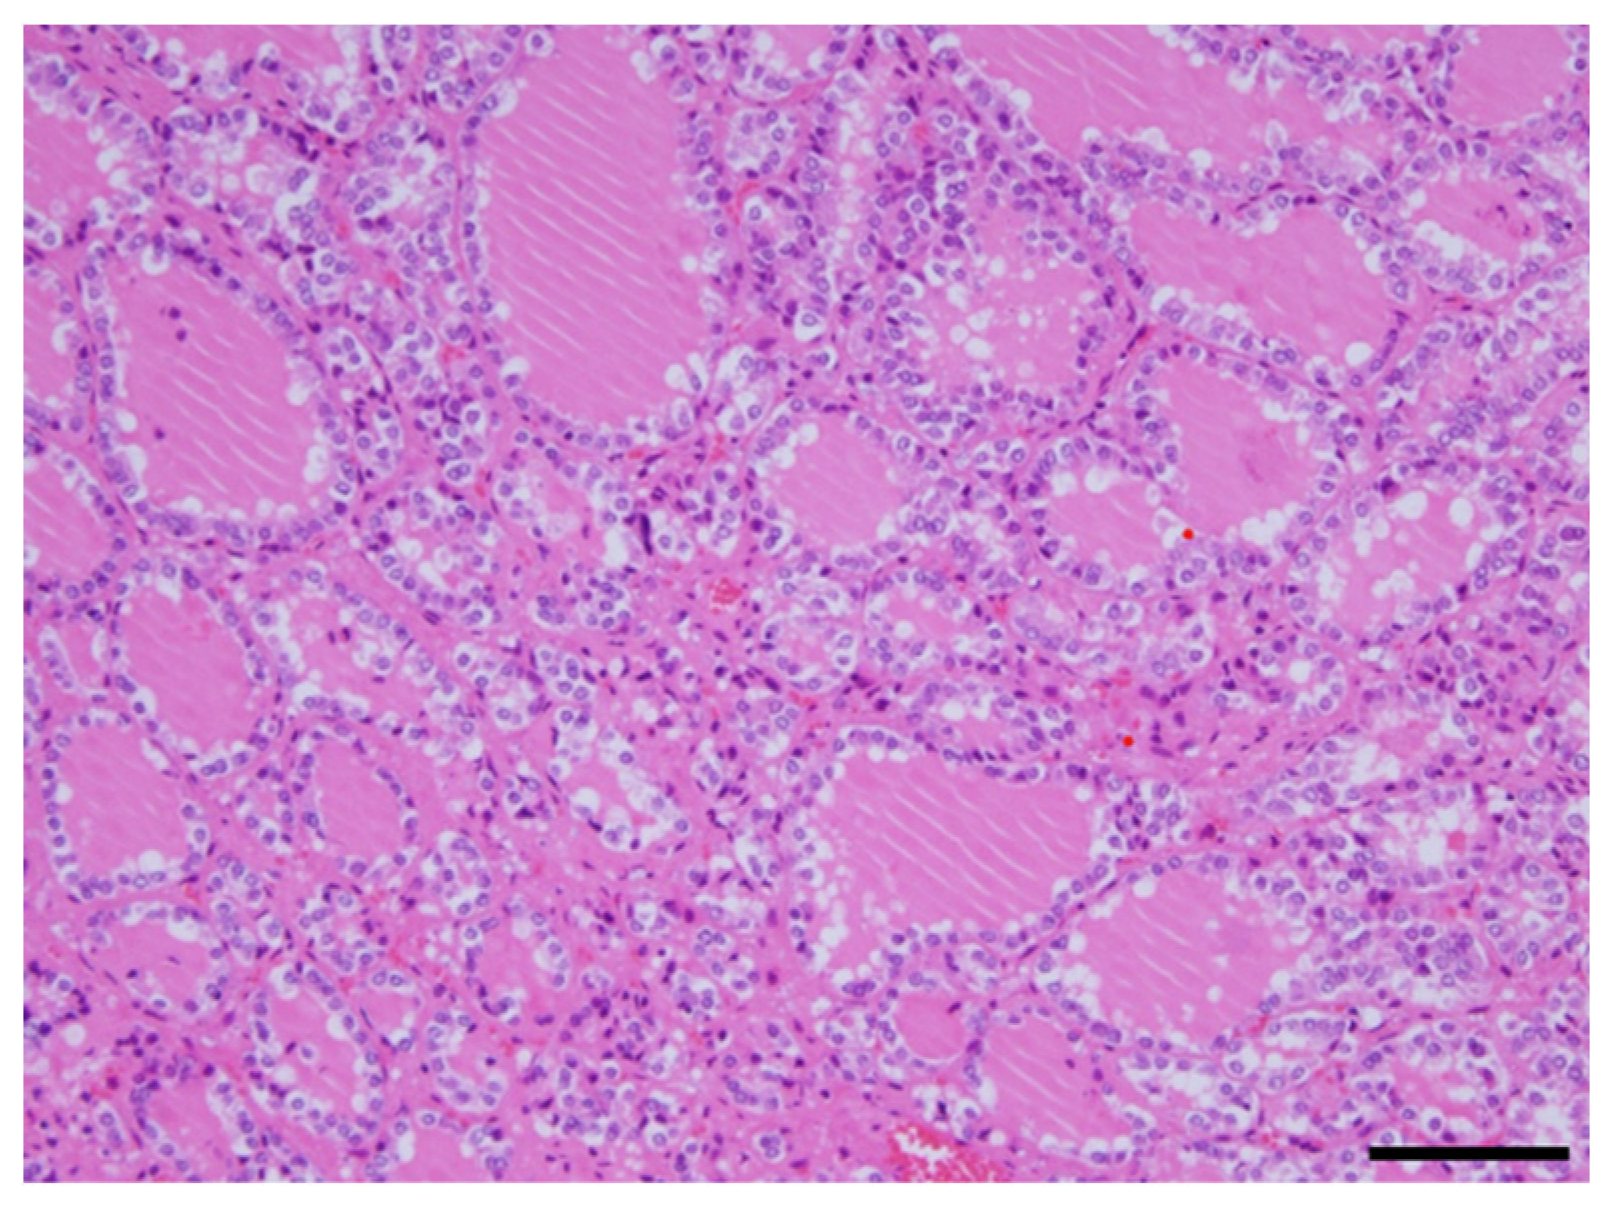

A 34-year-old woman was diagnosed with primary pulmonary hypertension (PPH). At that time, the current IPAH was called PPH. Then she underwent right heart catheterization, and her mean pulmonary artery pressure was 73 mmHg. She complained of dyspnea at rest corresponding to World Health Organization functional class IV. After diagnosing with PPH, she was treated with continuous intravenous epoprostenol. At 37 years of age, she started complaining of neck swelling. Thyroid studies showed Thyroid-stimulating hormone (TSH) = 0.01 μIU/mL (normal range: 0.35-4.94 μIU/mL), Free T3 = 19.88 pg/mL (normal range: 1.71-3.71 pg/mL), Free T4 = 4.86 pg/mL (normal range: 0.70-1.48 pg/mL), thyroid stimulating antibody = 465% (normal range: 0-180%), so she was diagnosed with Grave’s disease and prescribed thiamazole. Epoprostenol at this time was 15 ng/kg/min. Epoprostenol was titrated to decrease mean pulmonary artery pressure in combination with an endothelin receptor antagonist and a phosphodiesterase 5 inhibitor [10]. Epoprostenol maintained at 60-70 ng/kg/min after 14 years of treatment, and mean pulmonary artery pressure decreased to 30-35 mmHg. Thyroid function was controlled by therapy for Grave’s disease using thiamazole and levothyroxine. Nevertheless, her thyroid gland enlargement worsened as epoprostenol was titrated (Figure 1a, b). At 56 years of age, she was admitted to the local hospital due to worsening dyspnea. However, cardiogenic shock and respiratory failure with hypercarbonemia were observed, and she was transferred to our hospital the next day. At admission to our hospital, the patient’s vital signs were blood pressure of 97/62 mmHg, pulse of 117 bpm, and oxygen saturation of 88% with oxygen at 10 L/min through the mask. On examination, the auscultation revealed coarse crackles in her lungs and strider in her neck. Radiography of the chest revealed bilateral pulmonary congestion and airway stenosis (Figure 2a). Computed tomography of the chest also revealed airway stenosis by her giant goiter (Figure 2b). Blood gas analysis on 10 L/min of oxygen showed pH: 7.2, PaO2: 63.7 mmHg, PaCO2: 73.9 mmHg and HCO3-: 28.4 mmol/L, indicating respiratory failure with hypercarbonemia. Thyroid studies showed TSH = 2.265 μIU/mL, Free T3 = 1.52 pg/mL, Free T4 = 0.90 pg/mL. Tracheal intubation was difficult due to severe airway stenosis. Treatment with noninvasive positive pressure ventilation, dobutamine, and noradrenaline was ineffective, and she passed away on the 12th day after admission. Pathological autopsy was performed. Gross thyroid findings included diffuse enlargement (weight 675 g, size 14 cm x 6 cm) and compressive constriction of the upper airway by the thyroid gland (Figure 3). Histological findings of the thyroid gland showed increased thyroid follicle growth and increased colloidal resorption, suggesting a hyperthyroid state (Figure 4). There were no obvious malignant findings. The cause of death was considered to be respiratory failure due to airway narrowing caused by thyroid gland enlargement. The enlarged goiter was thought to be due to continuous intravenous epoprostenol therapy for IPAH.

Figure 4. Histological findings in the thyroid gland. The image of adenomatous goiter was presented. No malignant findings are observed. This showed increased thyroid follicle growth and increased colloidal resorption, suggesting a hyperthyroid state. Scale, 100 µm. HE staining.

We experienced a case of a massive goiter that led to airway stenosis during long-term continuous intravenous epoprostenol therapy. The enlarged goiter of this case doesn’t contradict hyperthyroidism according to Grave’s disease by the pathological findings. It is rare to report the enlarged goiter with airway stenosis by prostaglandin I2 derivatives. There is only one previously reported case of airway stenosis as in this case [11], but pathological findings are not discussed. This is the first case report of airway stenosis by giant goiter due to prostaglandin I2 derivatives which was also pathologically autopsied. There are two mechanisms of goiter by prostaglandin I2 derivatives. First, prostaglandin I2 receptor is expressed in the thyroid follicular cells, and prostaglandin I2 derivatives bind to this receptor and promote thyroid hormone synthesis [12]. Second, prostaglandin I2 derivatives active Th17 cells associated thyroid enlargement and Grave’s disease and promote the autoimmune response [13,14]. Although thyroid function was stable with thiamazole and levothyroxine in this case, her neck swelling was worsened. The cause was thought to be associated with the continuous intravenous epoprostenol therapy. Treatment for thyroid gland enlargement includes surgery or intra-iodine radiation therapy [15]. But it was reported that it was difficult to remove the giant goiter weighing more than 200 g due to the increased risk of hemorrhage generally [16], and the risk of perioperative mortality for patients with pulmonary hypertension is also high at approximately 8.3% [17]. Thus, her predicted perioperative mortality was high. Furthermore, as the enlarged thyroid gland became huge, the need for radioactive iodine became excessive, making oral administration of radioactive iodine difficult. The patient also had severe pulmonary hypertension on high-flow continuous intravenous epoprostenol therapy, making it difficult to interrupt epoprostenol. Therefore, proactive intervention for goiter swelling might be considered in the earlier stages of epoprostenol therapy for PAH.